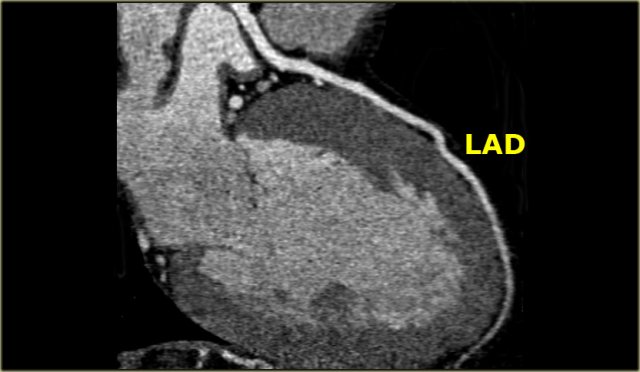

Left Anterior Descending (LAD)

The LAD travels in the anterior interventricular groove and continues up to the apex of the heart.

The LAD supplies the anterior part of the septum with septal branches and the anterior wall of the left ventricle with diagonal branches.

The LAD supplies most of the left ventricle and also the AV-bundle.

Mnemonic: Diagonal branches arise from the LAD.

The diagonal branches come off the LAD and run laterally to supply the antero-lateral wall of the left ventricle.

The first diagonal branch serves as the boundary between the proximal and mid portion of the LAD (2).

There can be one or more diagonal branches: D1, D2 , etc.